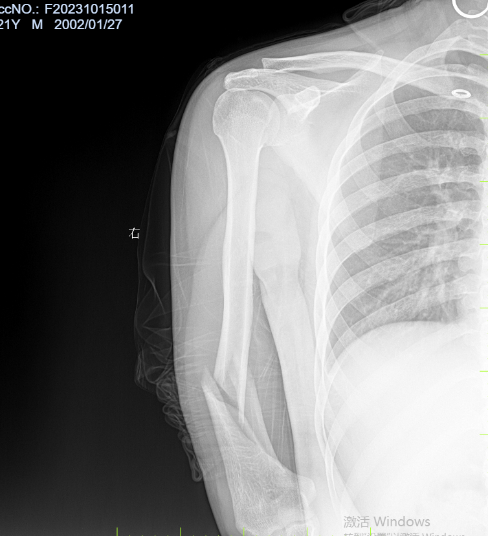

病例四:患者,男,21岁,因“与他人掰腕致右上肢疼痛伴活动受限5小时”入院。诊断:右肱骨干粉碎性骨折,桡神经损伤;行右肱骨干骨折切开复位内固定+桡神经探查修复术;手术顺利,术后进行康复训练中,功能恢复良好。

右肱骨干粉碎性骨折 术前X线片 右肱骨干粉碎性骨折 术前三维CT

右肱骨干粉碎性骨折 术后 X线片